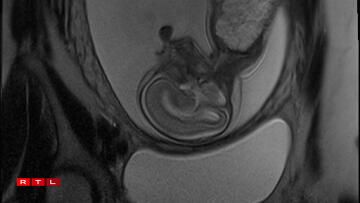

Lis was therefore referred to the Centre Hospitalier de Luxembourg (CHL), where further examinations led to a diagnosis. Noa was found to have a congenital pulmonary airway malformation (CPAM). Doctors explained that a large mass of cysts had formed in his chest, compressing his heart and disrupting his circulation. This, in turn, caused the fluid retention observed during the initial scan.

In Noa’s case, the CPAM was caused by a malformed aorta: a blood vessel had branched toward the lungs and was feeding the cysts. The condition is known as a sequestration. Professor Kohl proposed the following intervention:

“He would go through my abdomen with two small incisions to reach the amniotic sac, then pass through Noa’s chest to the heart, where he would cauterise the blood vessel that was feeding the cysts using a small electric current. From there, we could hope that the cysts would shrink and the lung could begin to develop”.